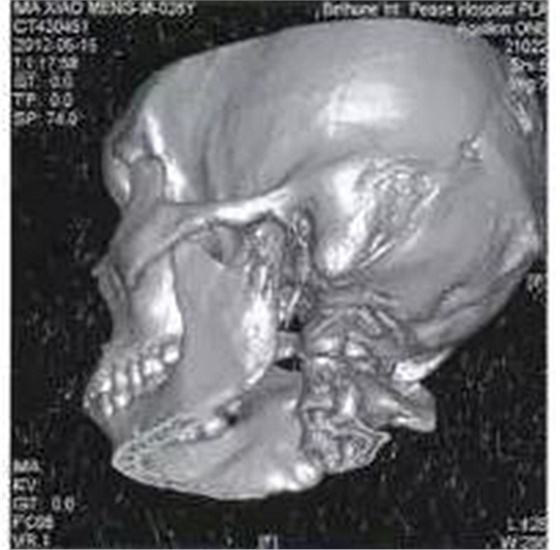

病例1,男,26歲。1月前在當(dāng)?shù)劓?zhèn)醫(yī)院拔除左上頜第三磨牙,術(shù)后3天出現(xiàn)左側(cè)面部腫脹,疼痛,張口受限,張口度約20mm,在當(dāng)?shù)剡M(jìn)行全身抗生素治療,局部未予任何處理,效果不佳。CT示左側(cè)咬肌間隙及顳下間隙腫脹,左側(cè)髁突頸部骨質(zhì)破壞,明顯死骨形成(圖1)。

圖1左側(cè)髁突骨髓炎,死骨形成

收入院后全麻下經(jīng)耳前顳部手術(shù)入路暴露病變區(qū)域,術(shù)中見左側(cè)髁突頸部外側(cè)骨皮質(zhì)破損,死骨分離。術(shù)中刮除死骨,貫通各個膿腔,引流膿液,放置引流條,抗感染治療,術(shù)后1月張口度恢復(fù)正常。